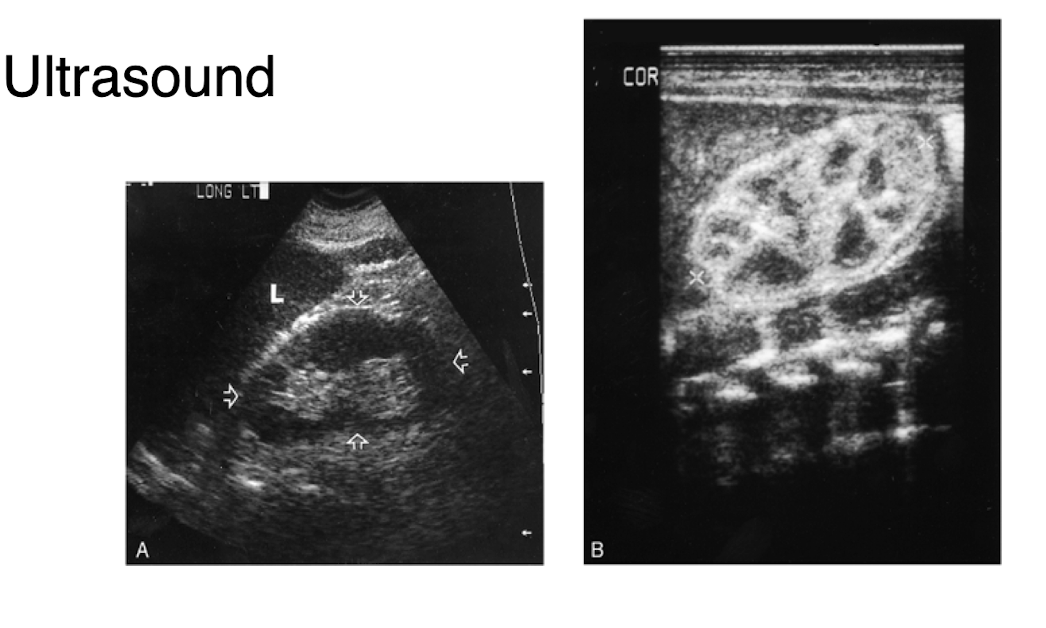

What is intussusception

A condition where a part of the intestine telescopes into an adjacent segment, causing obstruction and potential ischemia.

How is the diagnosis of intussusception confirmed and treated at the same time?

Diagnosis is typically confirmed through an abdominal ultrasound or CT scan, and treatment is performed via an air contrast enema or surgical intervention.